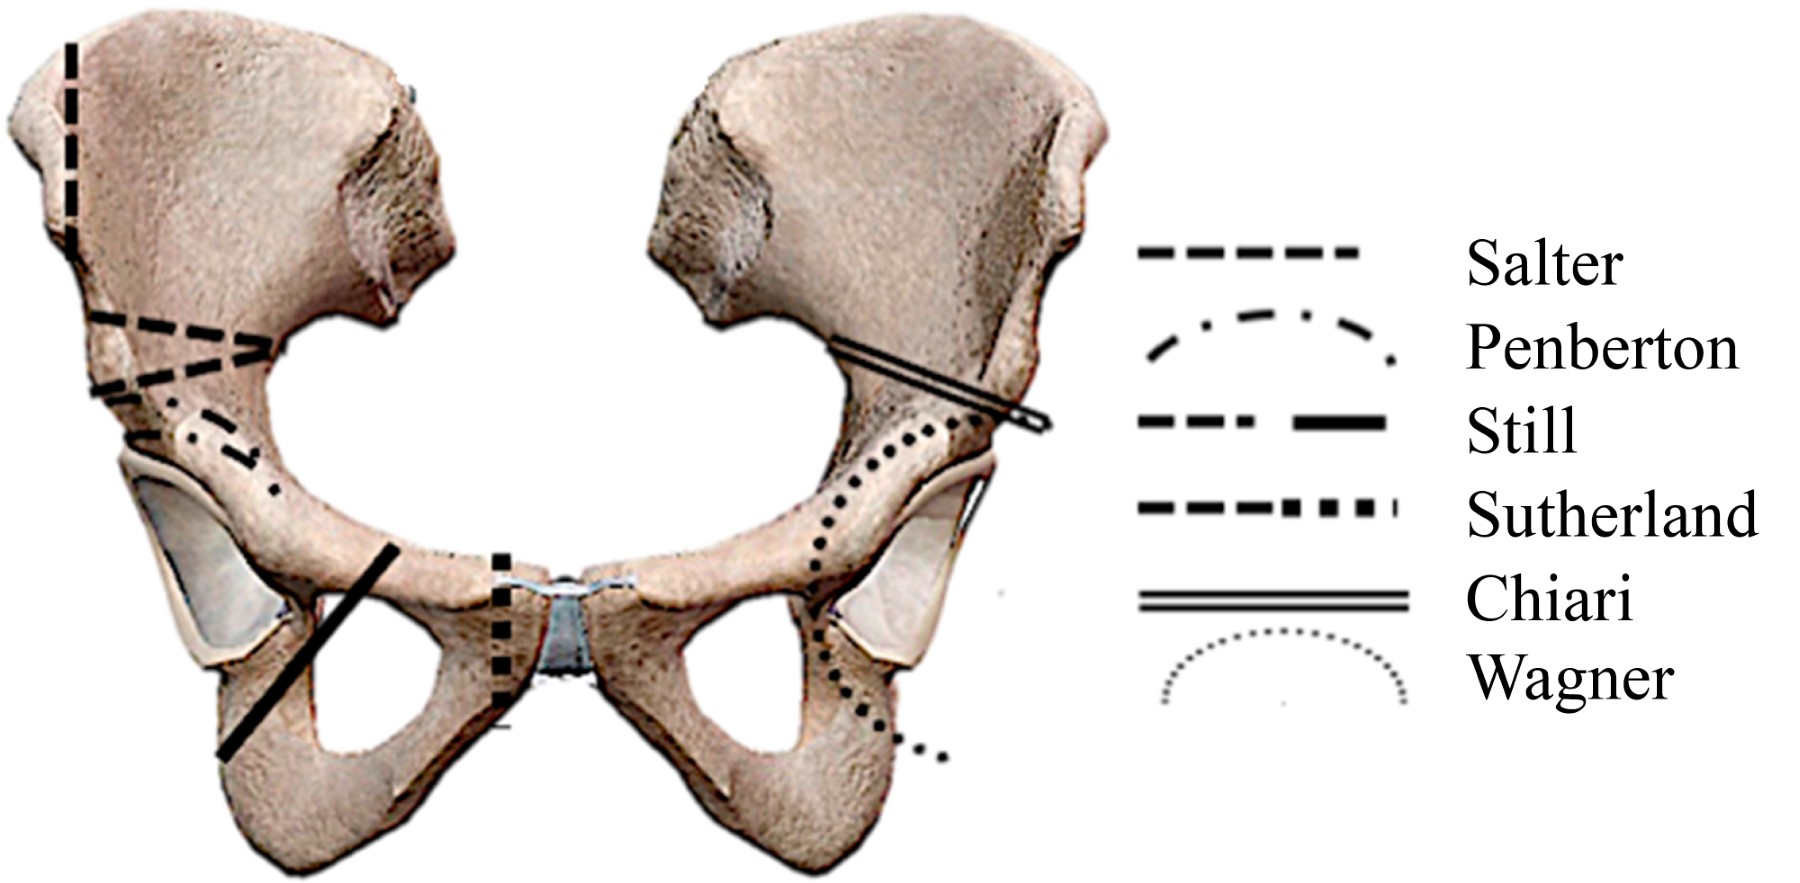

Osteotomías pélvicas

Las osteotomías pélvicas fueron ideadas principalmente para resolver el grave problema de las secuelas de una luxación congénita de la cadera no tratada o insuficientemente tratada. Han sido varios los autores que han contribuido con su experiencia y talento ideando diversos tipos de osteotomías (Figuras 3 y 4). El objetivo de éstas es reorientar el acetábulo en relación con la cabeza femoral, proporcionando cobertura y contención adecuada a la cabeza del fémur.

El pionero del tratamiento con osteotomías pélvicas fue Robert Bruce Salter,24 quien en 1961 hacía un corte de osteotomía supraacetabular en cuña en niños e introducía en ella un injerto óseo autólogo tomado de la cresta ilíaca para mantener la posición del acetábulo reorientado. Se usa como fulcro la sínfisis púbica.

La idea de reorientación acetabular de Salter fue seguida por diversos autores. David Hollingworth Sutherland25 en 1977 modificó la técnica de Salter al agregar al tradicional corte supraacetabular en ilíaco una osteotomía adicional cerca de la sínfisis del pubis. Llamó a esta técnica "doble osteotomía innominada".

Después de la innovación de Sutherland, quien propuso una doble osteotomía, Howard H. Steel26 siguió el mismo principio, pero lo hizo efectuando una triple osteotomía, osteotomizando el ilíaco, el isquion y el pubis separadamente. A esta técnica la llamó "triple osteotomía innominada". Esto ocurrió en 1973 (Figura 5).

Más tarde en 1981, Dietrich Tönnis27 hizo modificaciones a la técnica de triple osteotomía de Steel, proponiendo que los cortes de osteotomía no deben hacerse alejados de la articulación, sino por el contrario, lo más cerca posible. Con esta modificación buscó disminuir la limitante en la movilización del fragmento acetabular, que era ocasionada por los tejidos blandos que actúan como una brida dificultando su movilización, como ocurría con las osteotomías de Sutherland y Steel. La llamó "triple osteotomía yuxtaarticular" (Figura 6).

En 1955 Karl Chiari29 ideó una osteotomía que tiene un concepto totalmente diferente al resto de las osteotomías existentes en esa época para el tratamiento de la displasia acetabular. El procedimiento consiste en efectuar una osteotomía ilíaca supraacetabular completa, que permita el desplazamiento el fragmento inferior (trasfondo-cabeza) medialmente y el superior lateralmente. Esto produce una disminución del brazo de palanca medial y un aumento en la cobertura a la cabeza femoral por el fragmento ilíaco superior. El resto de la pelvis queda en su lugar de origen (Figura 7). El requisito indispensable es interponer la cápsula articular entre el fragmento superior desplazado y la cabeza femoral, la cual sufriría una metaplasia a fibrocartílago. Aunque desfigura el anillo pélvico, esta osteotomía fue muy popular, ya que técnicamente es muy fácil de hacer; sin embargo, con la aparición de las osteotomías periacetabulares y las prótesis de cadera prácticamente se ha abandonado.

Un hito en el tratamiento de la displasia acetabular en adultos con osteotomías fue el desarrollo de las osteotomías periacetabulares sin irrupción del anillo pélvico; los máximos representantes en este tipo de osteotomías fueron Heins Wagner30 y Reynold Ganz.31

Wagner30 en 1978 contribuyó de manera importante a este concepto con su osteotomía esférica periacetabular. Las osteotomías periacetabulares en general tienen la enorme ventaja de que no irrumpen la columna ni el muro posterior, dejando intacto el anillo pélvico. Por lo anterior, es mucho mejor la estabilidad que se obtiene en el fragmento libre acetabular osteotomizado. Otra ventaja es que se facilita el grado de cobertura de la cabeza femoral, y ya no se tiene la limitación de la movilización del fragmento acetabular al no intervenir de manera importante los tejidos blandos. Por lo anterior, se pueden obtener mucho mejores correcciones.

Sin duda, el que más contribuyó a la idea de las osteotomías periacetabulares fue Reynold Ganz,31 quien describió una osteotomía periacetabular que nombró "osteotomía bernesa" (Figuras 4 y 8). A esta osteotomía se le considera en la actualidad el estándar de oro para corregir las secuelas de las displasias acetabulares. Desafortunadamente, no es de utilidad cuando se aplica en casos avanzados de coxartrosis.